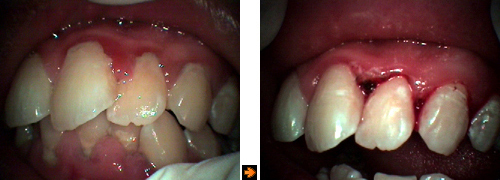

歯周病初期の治療

![]()

↑治療前: |

↑治療後1週間: |